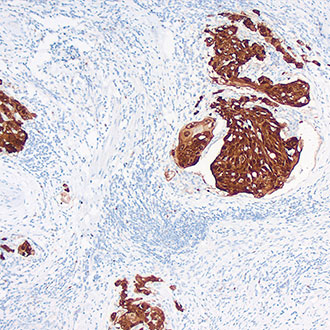

Cyclin D1

Cyclin D1 -